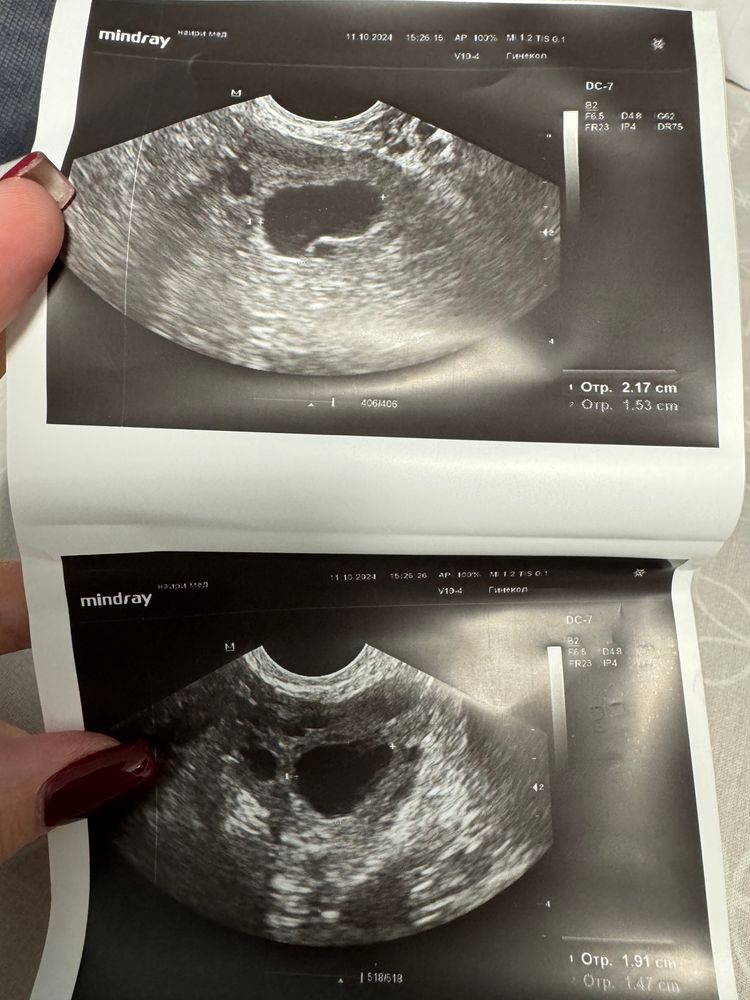

Дарья, да он как-то медленно растет.. и формы такой странной.. вытянутый более, что ли.. вот он был на 1 фотке и вот 2 это сейчас 🤔 Изображение Изображение

Алена, да, фолликул интересной формы такой 🤭